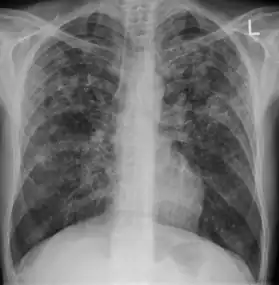

In active pulmonary TB, infiltrates or consolidations and/or cavities are often seen in the upper lungs with or without mediastinal or hilar lymphadenopathy.[1] However, lesions may appear anywhere in the lungs. In HIV and other immunosuppressed persons, any abnormality may indicate TB or the chest X-ray may even appear entirely normal.[1]

Old healed tuberculosis usually presents as pulmonary nodules in the hilar area or upper lobes, with or without fibrotic scars and volume loss.[1] Bronchiectasis and pleural scarring may be present.

Abnormalities on chest radiographs may be suggestive of, but are never diagnostic of, TB.[1] However, if a person has a positive response to the tuberculin skin test and no symptoms of the disease, chest radiographs can be used to rule out the possibility of pulmonary TB.